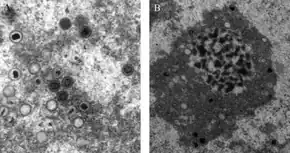

Transmission electron microscope (TEM) image of cytomegalovirus (CMV) virions that were present in a (unknown) tissue sample. | |